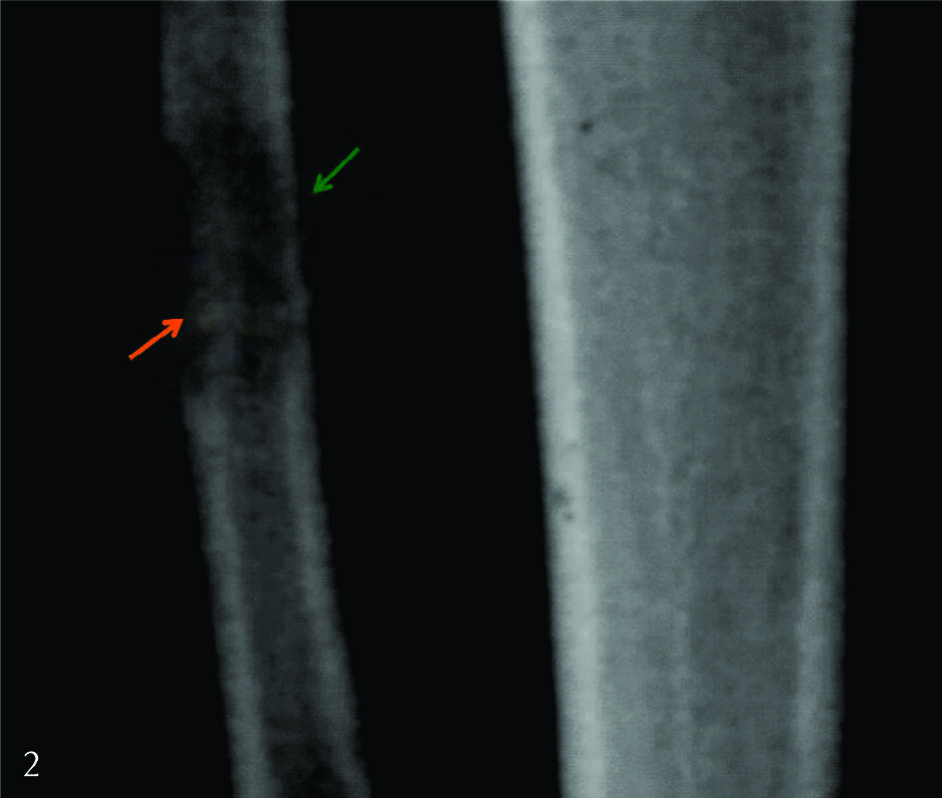

Figura 2

Radiografía de frente con aumento del área de interés.

La lesión proximal presentaba reacción perióstica de tipo continua (flecha verde) en asociación a un trazo esclerótico en relación a factura patológica evolucionada (flecha naranja). El resto de las lesiones no presentaban reacción perióstica.